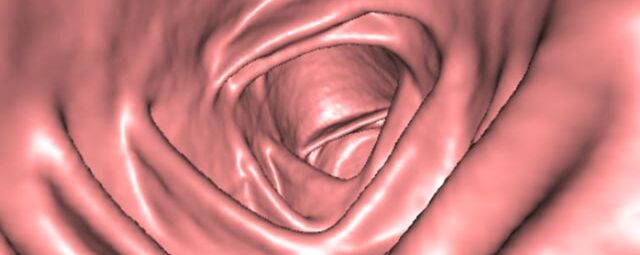

• Virtuelle Kolonographie zur Darstellung des Dickdarmes z. B. bei Kontraindikation zur Darm-Spiegelung oder nur unvollständig durchführbarer Koloskopie.